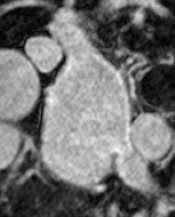

Automated segmentation in medical image analysis is a challenging task that requires a large amount of manually labeled data. However, most existing learning-based approaches usually suffer from limited manually annotated medical data, which poses a major practical problem for accurate and robust medical image segmentation. In addition, most existing semi-supervised approaches are usually not robust compared with the supervised counterparts, and also lack explicit modeling of geometric structure and semantic information, both of which limit the segmentation accuracy. In this work, we present SimCVD, a simple contrastive distillation framework that significantly advances state-of-the-art voxel-wise representation learning. We first describe an unsupervised training strategy, which takes two views of an input volume and predicts their signed distance maps of object boundaries in a contrastive objective, with only two independent dropout as mask. This simple approach works surprisingly well, performing on the same level as previous fully supervised methods with much less labeled data. We hypothesize that dropout can be viewed as a minimal form of data augmentation and makes the network robust to representation collapse. Then, we propose to perform structural distillation by distilling pair-wise similarities. We evaluate SimCVD on two popular datasets: the Left Atrial Segmentation Challenge (LA) and the NIH pancreas CT dataset. The results on the LA dataset demonstrate that, in two types of labeled ratios (i.e., 20% and 10%), SimCVD achieves an average Dice score of 90.85% and 89.03% respectively, a 0.91% and 2.22% improvement compared to previous best results. Our method can be trained in an end-to-end fashion, showing the promise of utilizing SimCVD as a general framework for downstream tasks, such as medical image synthesis and registration.